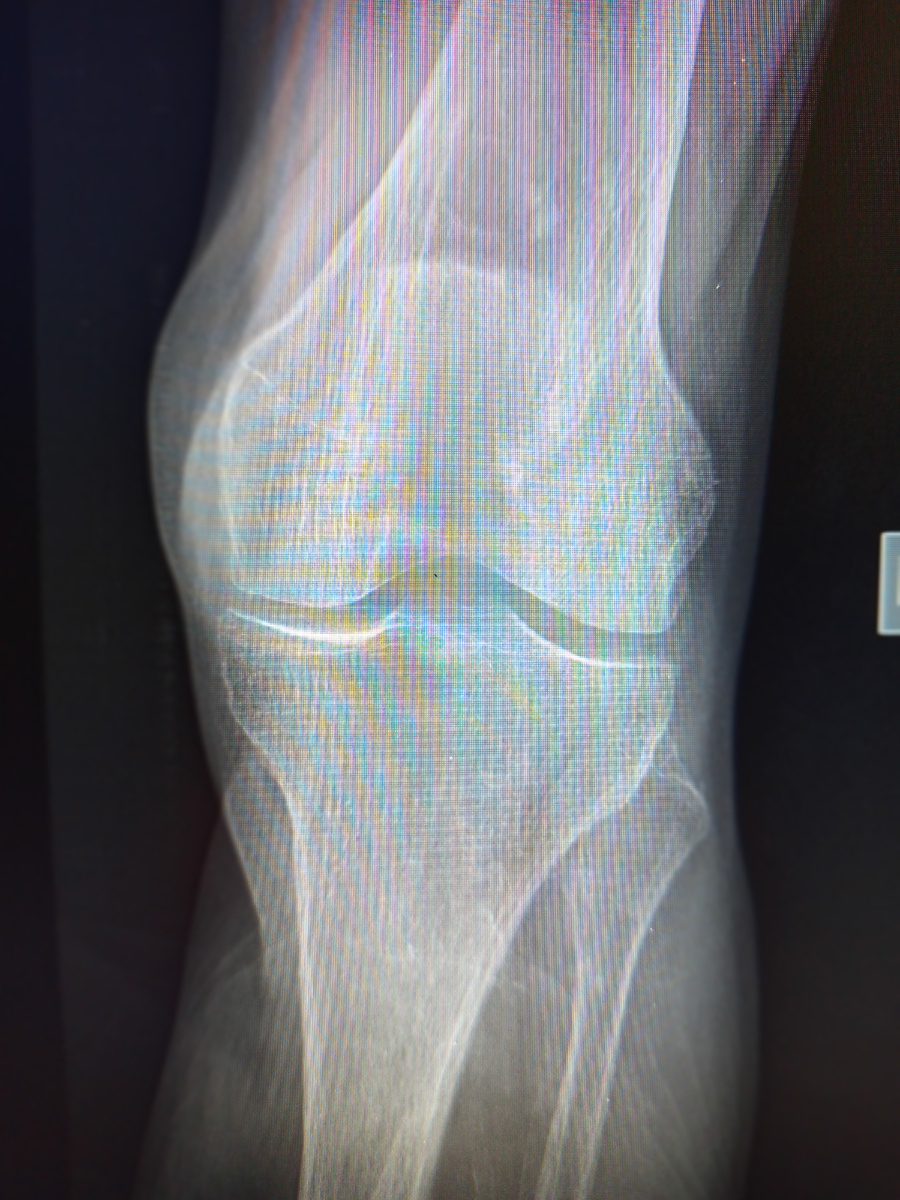

Я насмотрелась на различные патологии суставов у молодых и не очень пациентов, но тут даже я позавидовала

"Завидувайте" молча , что называется! 92 года! Да, так бывает, оказывается.